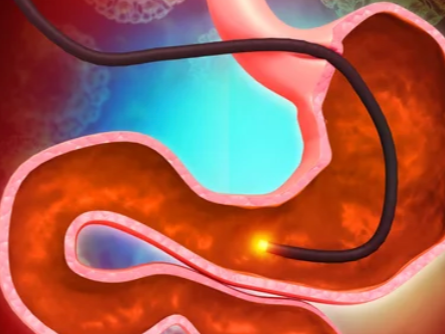

위내시경은 위 점막의 병변을 직접 확인할 수 있는 가장 정밀한 검사지만, 눈으로 보는 것만으로는 병의 본질을 100% 파악할 수 없습니다. 겉으로는 단순 염증처럼 보여도 실제로는 암세포가 존재할 수 있고, 반대로 악성처럼 보이는 병변이 양성일 수도 있습니다. 이런 시각적 한계를 보완하기 위해 시행되는 것이 바로 ‘조직검사’입니다. 조직검사는 위내시경 중에 의심되는 부위에서 작은 조직을 채취해 현미경으로 분석하는 과정으로, 세포의 형태와 배열, 염증 정도, 암세포 존재 여부 등을 확인해 최종 진단을 내립니다.

위 내시경 중 시야를 확보하면서 의심 부위를 찾으면, 내시경 기구 끝에 있는 ‘겸자’를 이용해 조직을 2~4조각 정도 채취합니다. 병변이 넓거나 불균일할 경우, 여러 위치에서 추가로 채취합니다.